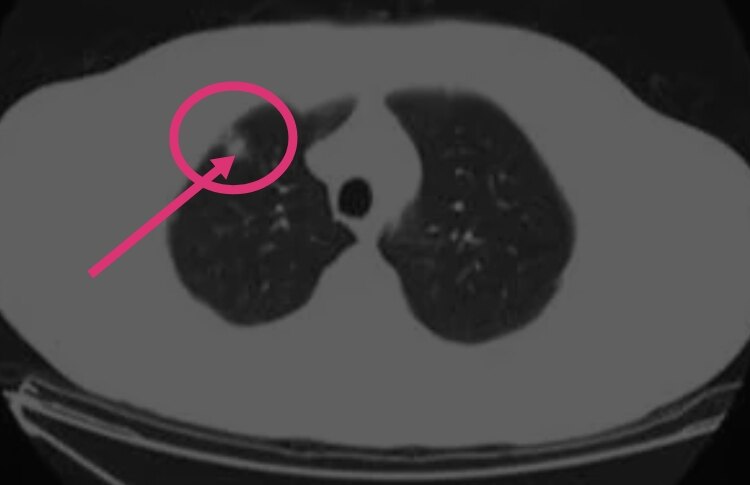

如果患者持续出现疼痛,且伴有高热等,则需要行相关检查,包括胸部CT以及血常规检查,排除是否伴有胸腔内感染或者肺脓肿形成的情况。